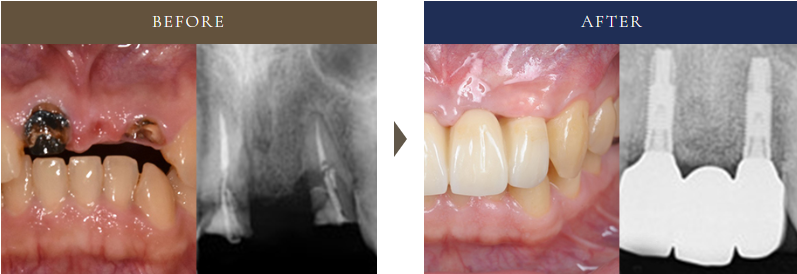

4-4:治療実例|ブリッジからインプラントへ切り替えたケース

50代女性の患者さま。

保険診療で装着した、3本連結のブリッジにぐらつきが出て来院されました。

診断の結果、支台歯の2本に進行した虫歯があり、残すのが難しい状態。

- 何度も治療を繰り返したくない

- 長く安心して使える治療法を選びたい

とのご希望から、抜歯後に2本のインプラントで補綴治療を実施しました。

現在は5年以上経過しても安定して使用できており、「しっかり噛めるし違和感がない」と高い満足感を得られています。

- 治療期間:約11ヶ月

- 費用:822,000円(税込904,200円)

- 補足:CT診断と治療用ガイドを活用し、安全性に配慮。大規模な骨造成を行い、機能性だけでなく審美性にも配慮した治療を行いました。